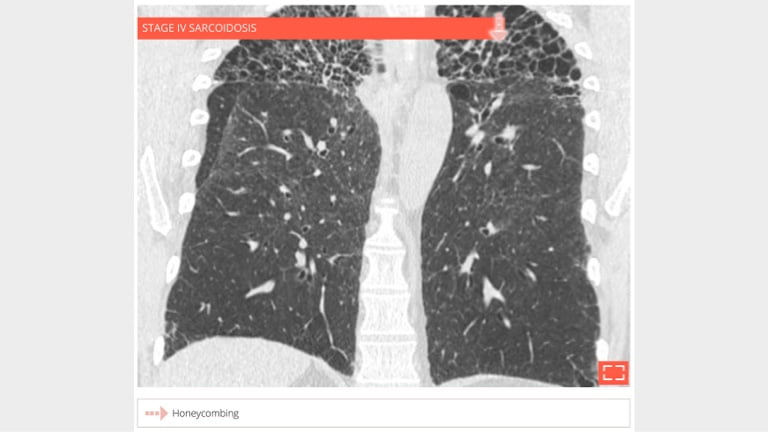

4. Honeycombing

honey-4

56-year-old man with history of sarcoidosis. Typical honeycombing in a upper lobe distribution.

5. Honeycombing

honey-5

• Coronal reformation in the same patient shows the association of honeycombing and reticulation in lung apices.

• Distribution of fibrosis to apices makes this fibrosis incompatible with UIP.